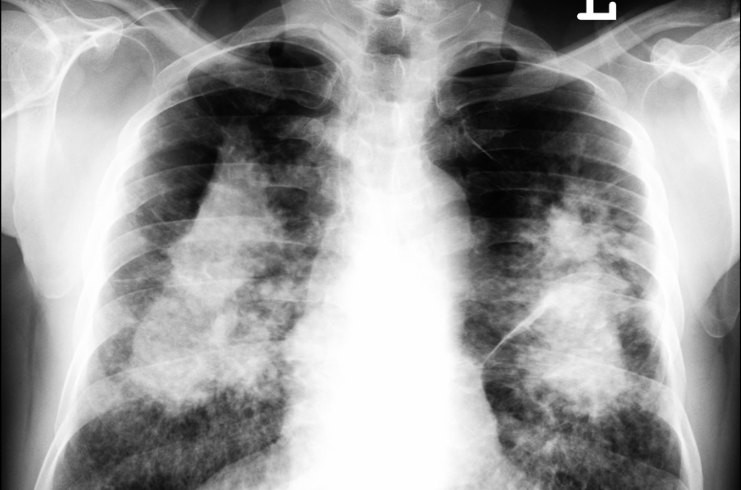

Silicosi

- Descrizione: Malattia respiratoria causata dal deposito di particelle di biossido di silicio, nelle vie respiratorie. È considerata irreversibile e invalidante.